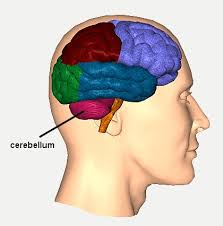

Brain Anatomy

To fully understand what happens to an injured brain, it is important to know the basic anatomy and function of a healthy brain. The brain is safely enclosed inside the protective covering of the skull. A brain is made of nerve cells (neurons) that form routing pathways that run throughout the brain and body. The function of these pathways or tracts is to deliver messages like breathing; regulating body temperature, heart rate, metabolic activities, and controlling behavior, personality, thoughts, and the five senses of smell, touch, vision, taste and hearing. The brain is made up of six parts.

- Frontal lobes

- Temporal lobes

- Parietal lobes

- Occipital lobes

- Brain stem

- Cerebellum

Frontal Lobes

This part of the brain is responsible for behavioral output (social and cognitive behaviors), as well as body movement. Some of the many behaviors and functions of the human brain include: inhibition; behavior initiation and self-regulation; abstract reasoning; attention and working memory; executive functioning (multitasking, organizing, etc.); and movement (muscles involved in speech, facial expressions, etc.).This brain region is often affected by TBI from motor vehicle accidents, especially injuries caused by rapid acceleration-deceleration type events.

Temporal Lobes

This region of the brain is comprised of the primary auditory cortex and areas of the brain involved in the comprehension and production of spoken language (speech center of the brain). They are also responsible for memory development and learning. The temporal lobes are associated with several behaviors and functions of the human brain that include processing of auditory input; comprehension of spoken language; language production (choosing the appropriate words and fluency of spoken speech); and verbal and visual memory.

Parietal lobes

The parietal lobes are responsible for complex behaviors, including all behavior involving the senses. They are also involved in body positioning and movement; sensory perception; sensory neglect; language comprehension; constructional ability; right-left differentiation; self-awareness; and the ability to perform mathematical calculation.

Occipital Lobes

This region includes the primary visual cortex and the visual association areas of the brain. Injury to the occipital lobes may lead to vision impairments such as blindness or blind spots; visual distortions and visual inattention. The occipital lobes are also associated with various behaviors and functions that include: visual recognition; visual attention; and spatial analysis.

Brain stem

The brain stem is located at the very base of the human brain and assists in a many of the body’s most important functions. A few of its vital functions is to assist in breathing; heart rate; swallowing; controlling blood pressure, digestion, temperature; regulating an individual’s level of alertness, ability to sleep, and sense of balance.

Cerebellum

The cerebellum is located directly above the brain stem. It is responsible for controlling the coordination of voluntary movement; balance and equilibrium. It also controls and develops memory for fine reflex motor acts.